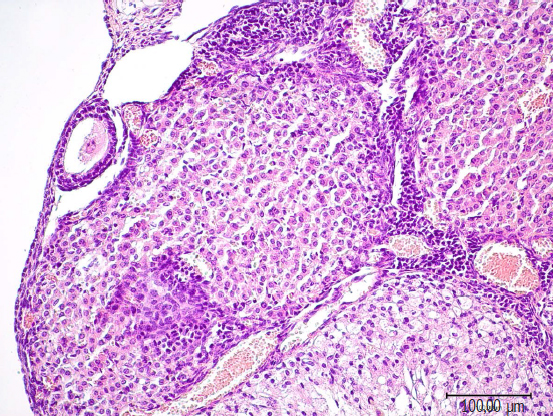

Обсуждение. В яичниках потомства первой экспериментальной группы С-50 наблюдаются стойкие морфологические изменения: увеличение средней площади коркового вещества, уменьшение показателей площади мозгового вещества, увеличение среднего количества желтых тел, увеличение среднего количества лютеиновых клеток в желтом теле, снижение суммарного количества фолликулов и атретических тел, свидетельствующие о нарушении процесса фолликулогенеза, увеличение среднего диаметра кровеносных сосудов, демонстрирующие усиление кровообращения. При введении препарата фулвестранта в дозе 100 мкг/кг во второй экспериментальной группе Ф-100 на срезе яичников потомства рассматриваются морфологические изменения в виде увеличения средней площади коркового вещества, уменьшения средней площади мозгового вещества, склерозирования стромального компонента, сопровождающегося перестройкой сосудистой сети с признаками атрезии и кистозного перерождения фолликулярного эпителия во вторичных и третичных фолликулах.